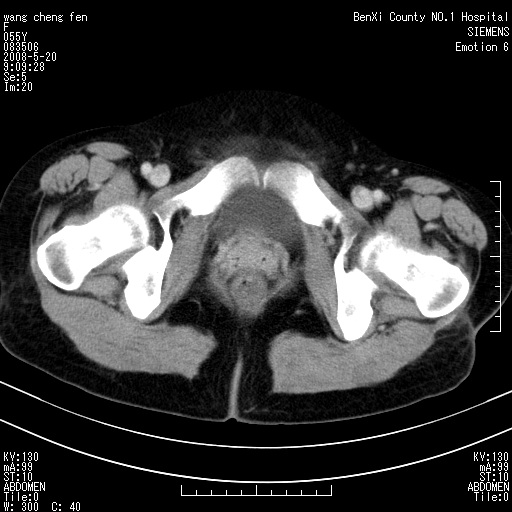

女、绝经后阴道流血3个月

左侧附件区巨大囊实性病灶,边缘光整,病灶囊壁较厚,增强示囊壁及实性部分明显强化,强化呈度与宫体实质大致相同,宫腔积液征像,未见盆腔积液等其他异常,考虑左侧卵巢囊腺癌,不除外囊腺瘤及浆膜下肌瘤坏死

左侧附件区巨大囊实性病灶,边缘光整,病灶囊壁较厚,增强示囊壁及实性部分明显强化,强化呈度与宫体实质大致相同,宫腔积液征像,未见盆腔积液等其他异常。绝经后阴道流血3个月,结合病史左侧卵巢囊腺癌首先考虑,宫腔扩大不除外累及。期待结果。

考虑巨大的浆膜下子宫肌瘤并变性坏死,宫颈周围静脉曲张。

1,宫颈部占位,宫颈癌?2,左侧附件区囊实性占位,界较清,实质部分强化明显。考虑浆膜下或阔韧带肌瘤囊变可能大。囊腺类肿瘤不除外。